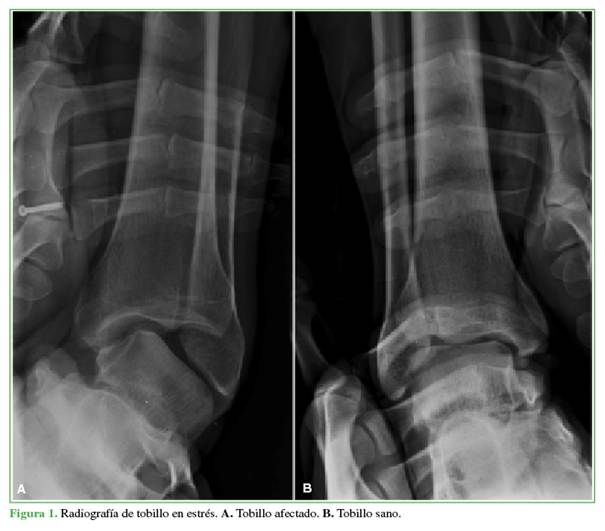

Para evaluar la reparación del complejo ligamentario lateral, a los 6 meses de la cirugía, se solicitó una radiografía en estrés (Figura 3). En la evaluación clínico-funcional, se utilizaron la escala de la AOFAS (American Orthopaedic Foot and Ankle Society) y la escala analógica visual.